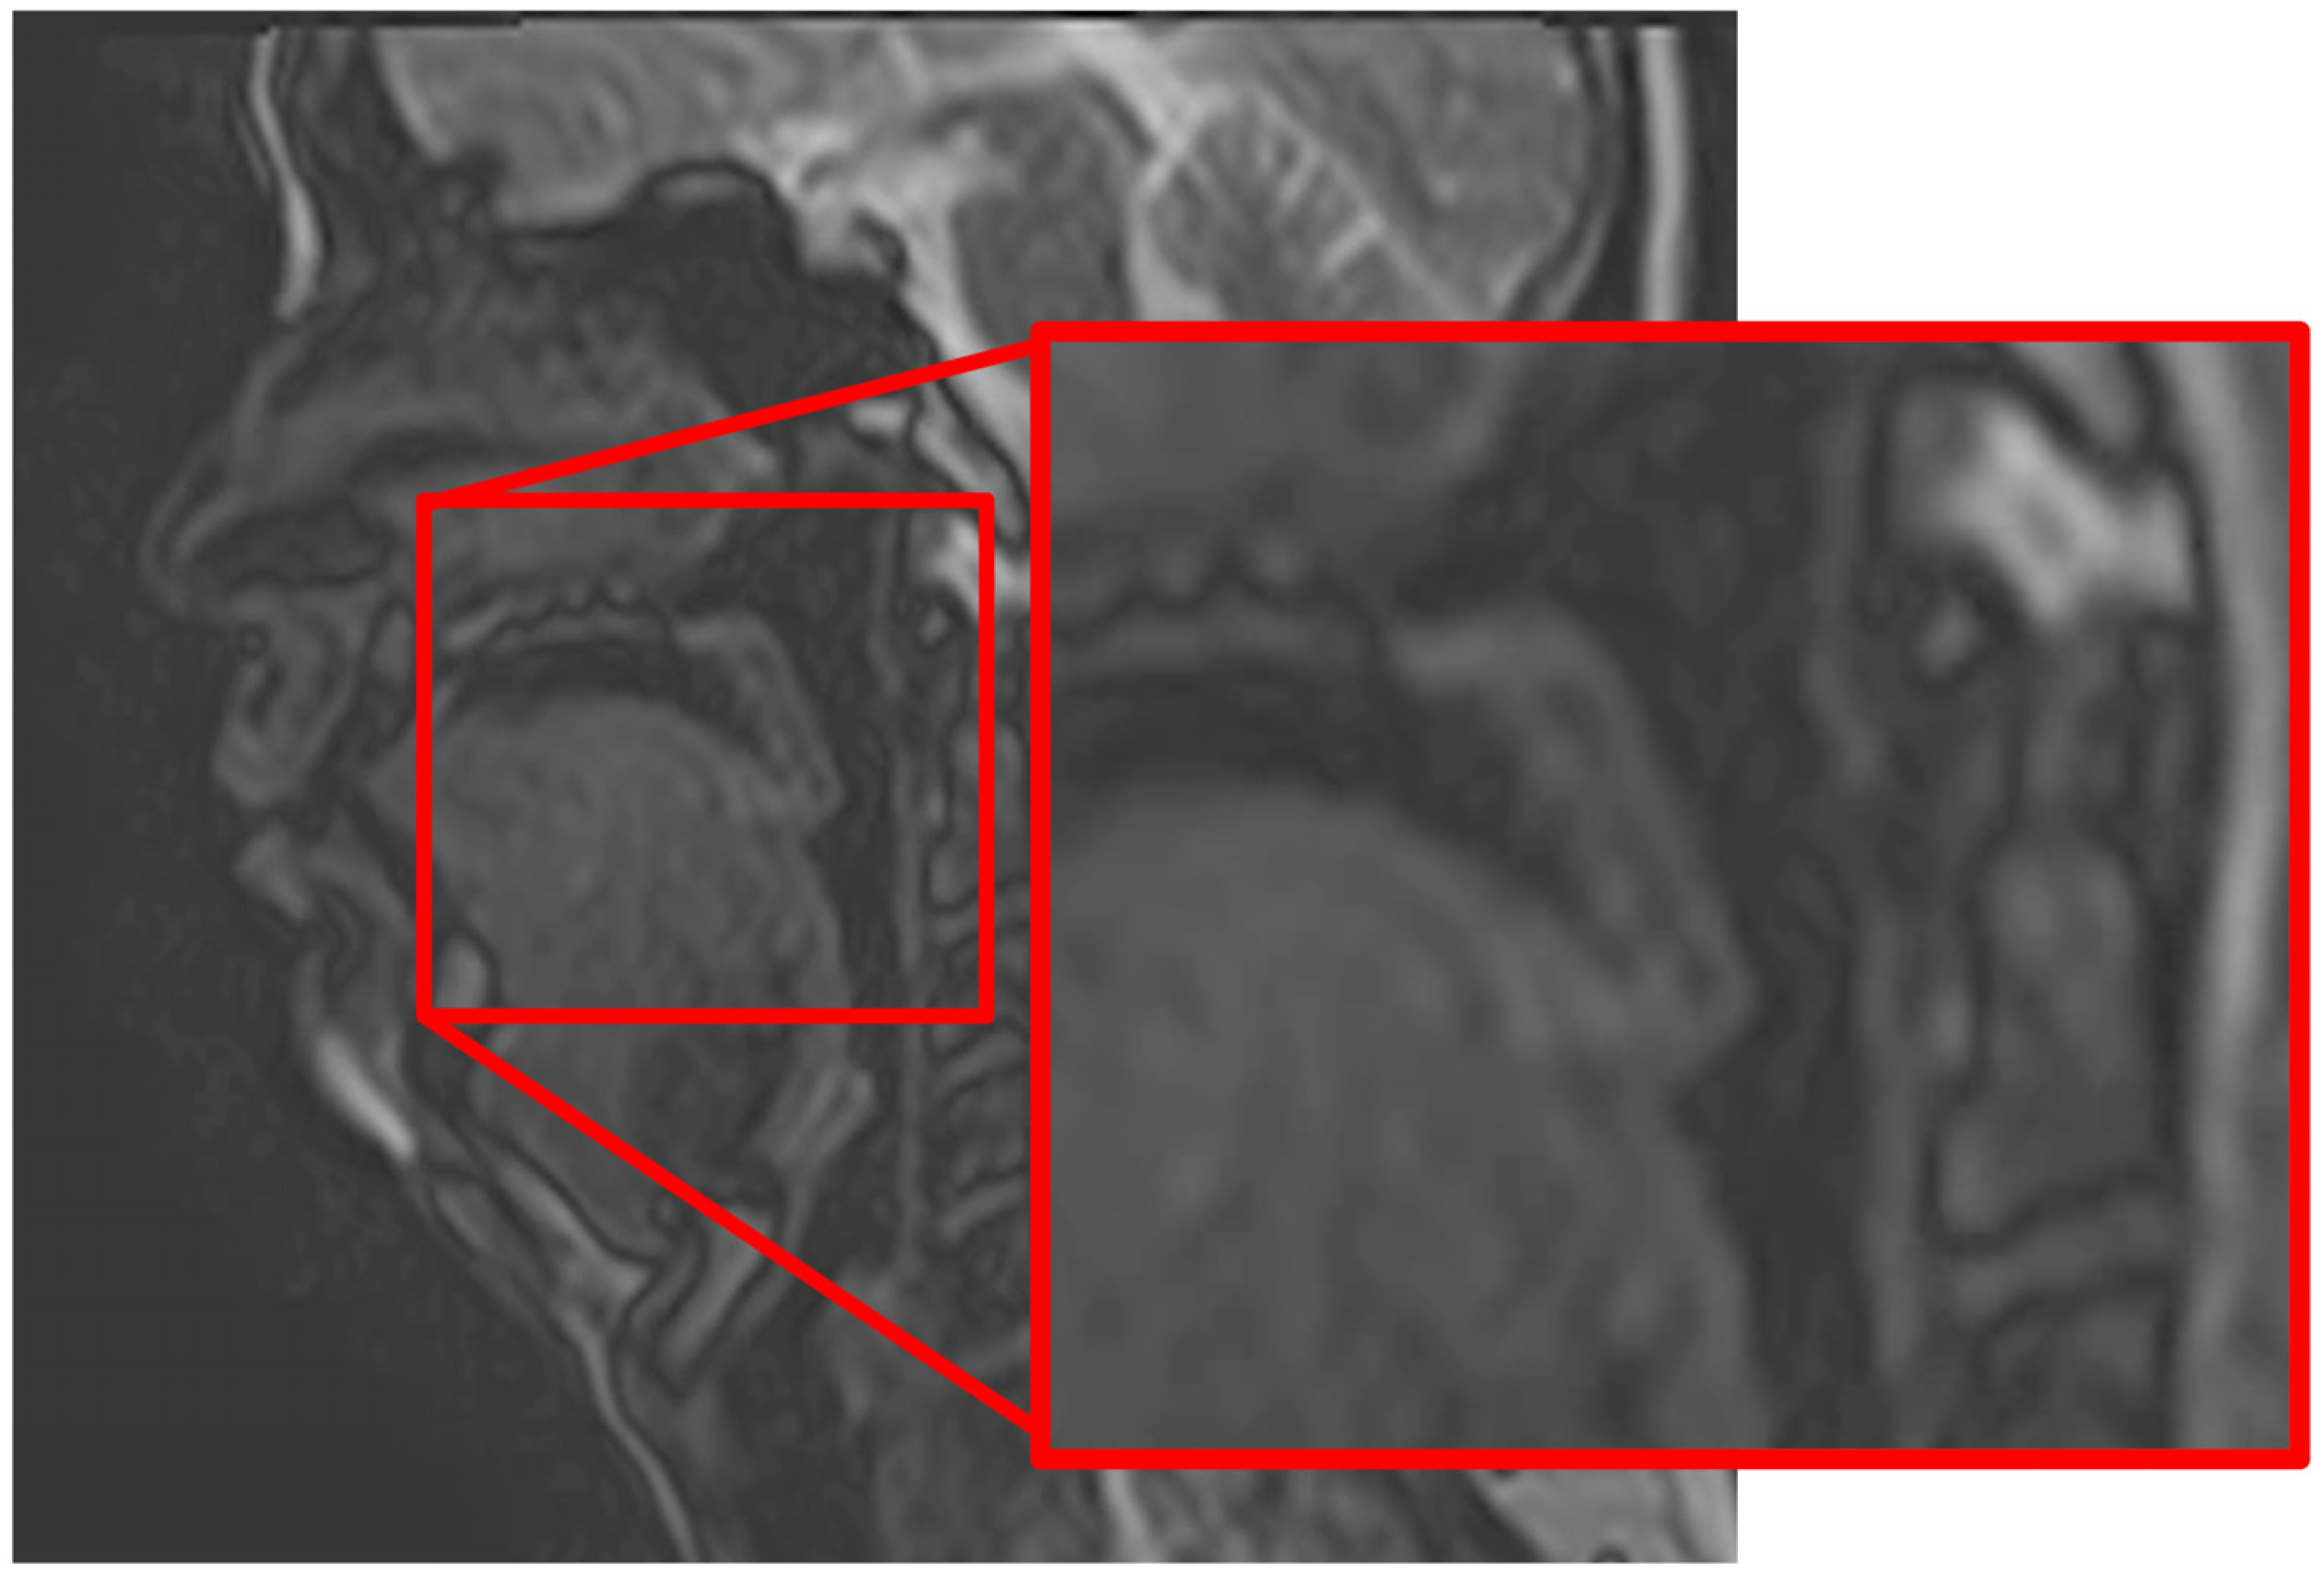

- Joujima, T.; Oda, M.; Sasaguri, M.; Habu, M.; Kataoka, S.; Miyamura, Y.; Wakasui-Sato, N.; Matsumoto-Takeda, S.; Takahashi, O.; Kokuryo, S.; et al. Evaluations of velopharyngeal function using high-speed cine-MRI based on T2-weighted sequences: A preliminary study. Int. J. Oral Maxillofac. Surg. 2020, 49, 432–441. [Google Scholar] [CrossRef]

- Morimoto, Y.; Tominaga, K.; Konoo, T.; Tanaka, T.; Ohba, T. Detection and significance of the characteristic magnetic resonance signals of mandibular condyles in children. Oral Surg. Oral Med. Oral Pathol. Oral Radiol. Endod. 2004, 97, 269–275. [Google Scholar] [CrossRef]

- Morimoto, Y.; Tominaga, K.; Konoo, T.; Tanaka, T.; Yamaguchi, K.; Fukuda, J.; Ohba, T. Alternation of the magnetic resonance signals characteristic of mandibular condyles during growth. Oral Surg. Oral Med. Oral Pathol. Oral Radiol. Endod. 2004, 98, 348–354. [Google Scholar]

- Morimoto, Y.; Konoo, T.; Tominaga, K.; Tanaka, T.; Yamaguchi, K.; Fukuda, J.; Ohba, T. Relationship between cortical bone formation on mandibular condyles and alternation of the magnetic resonance signals characteristic during growth. Am. J. Orthod. Dentofac. Orthop. 2007, 131, 473–480. [Google Scholar] [CrossRef] [PubMed]